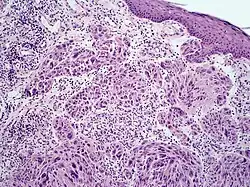

Melanoma with features of a Spitz nevus, also known as a Spitzoid melanoma, is a cutaneous condition characterized histologically with tissue similar to a spitz nevus and with overall symmetry and a dermal nodule of epithelioid melanocytes that do not mature with progressively deeper dermal extension.[1]